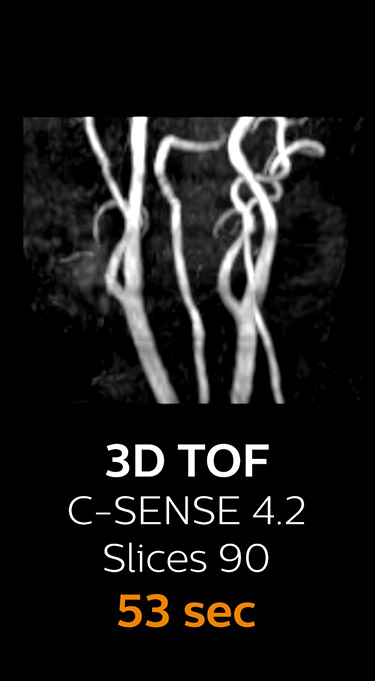

Fast MRI of cervical spine

With Compressed SENSE, the scan time for the routine cervical spine examination at KNC was reduced from 13:11 to 9:52 minutes, which corresponds to 25% reduction.

MRI examination of the cervical spine with Compressed SENSE

Ingenia 3.0T CX

Scan time 9:52 min. (was 13:11 min. without Compressed SENSE)